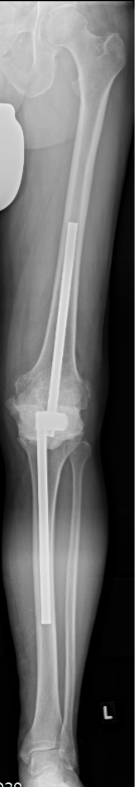

Once the site has been correctly prepared and cleaned, suitable AO hollow steel rods are selected that are available in a diameter of 12 mm and lengths from 100 mm to 450 mm (Fig. 1).

Manual diaphyseal press-fit anchoring represents the target and the length of the AO rods is chosen with the objective of achieving the most stable intramedullary anchoring (Fig. 2).

This should involve the rod extending far enough beyond the resection line into the joint space to facilitate the installation of the tube-to-tube connecting clamp (connector) (Fig. 3).

X-ray monitoring

As a precaution, the final check by X-ray imaging should be performed before the final closing of the joint. This should assess the distribution of the cement (specifically a dorsal penetration of cement) and the integrity of the femoral and tibial diaphyseal bone. Postoperative options for X-ray assessment are a long anteroposterior view with distal femur and proximal tibia or whole leg standing X-ray image to document that the limb alignment is neutral, as well as a lateral view of the knee joint to assess the cement spacer (Fig. 2 and 3).